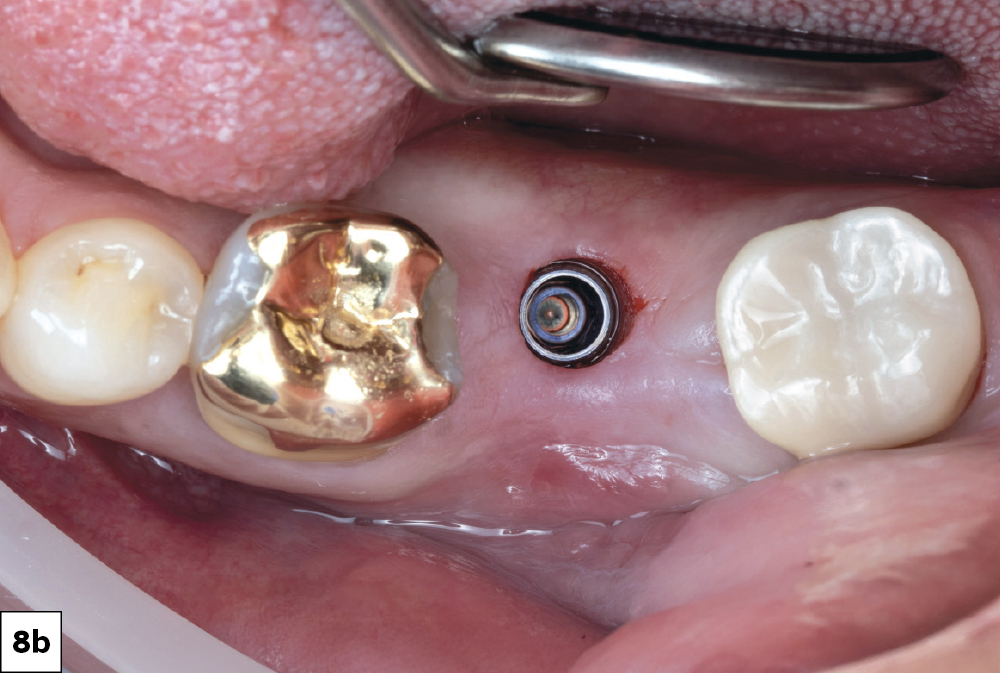

Tissue punch in socket #18

Guided drilling protocol

Glidewell HT Implant torqued into place

Figures 8a–8c: Due to the sufficient amount of attached gingiva and the precise positioning of the guide, a minimally invasive tissue punch was made to expose the site for the guided drilling protocol. A 5 mm Glidewell HT™ Implant was torqued into place at 45 Ncm and a Glidewell HT Implant Healing Abutment was placed for four months of healing (Glidewell Direct).